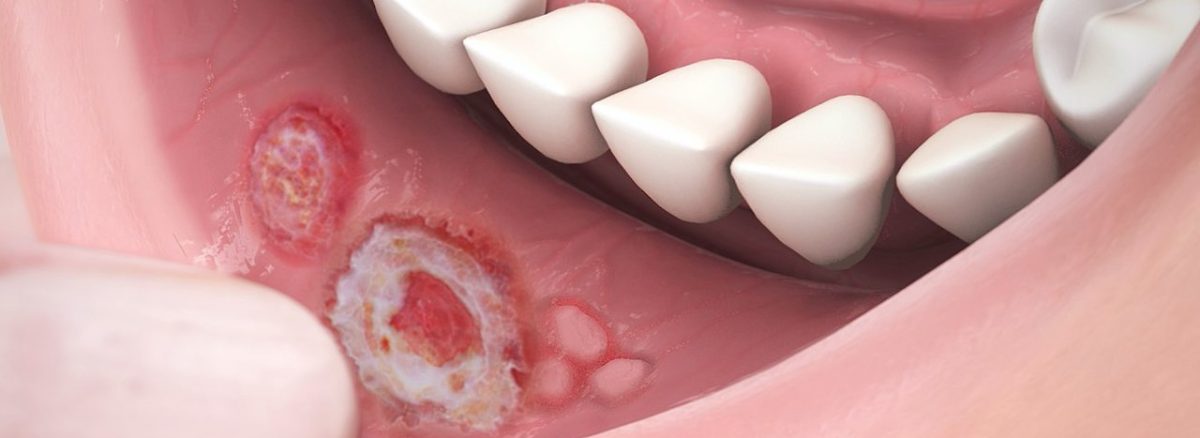

- التهاب و تورم دهانی: التهاب، تورم، قرمزی یا آفتها در دهان ممکن است بیماریهای لثه، زخم دهانی، عفونتهای قارچی یا ویروسی را نشان دهند.

نشانههایی مانند درد و تورم دهان و لثه، خونریزی لثه، تغییر رنگ و سنگین شدن دندانها، بوی بد دهان، قسمتهای زخمی یا قرمز روی دهان، خزش و لرزش دندانها و ریزش لکههای سفید بر روی زبان میتواند به بیماری دهان و دندان اشاره کند.